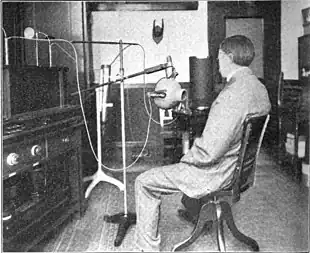

Historically conventional external beam radiation therapy (2DXRT) was delivered via two-dimensional beams using kilovoltage therapy X-ray units, medical linear accelerators that generate high-energy X-rays, or with machines that were similar to a linear accelerator in appearance, but used a sealed radioactive source like the one shown above.[71][72] 2DXRT mainly consists of a single beam of radiation delivered to the patient from several directions: often front or back, and both sides.